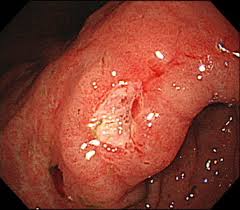

DAY SURGERY 日帰りポリープ手術

当院は「日帰り手術大腸ポリープ」を行っています。

例えば、大腸内視鏡検査を行った際に大腸ポリープが見つかり、切除が必要と判断すれば、その日のうちに切除を行うことも可能です。